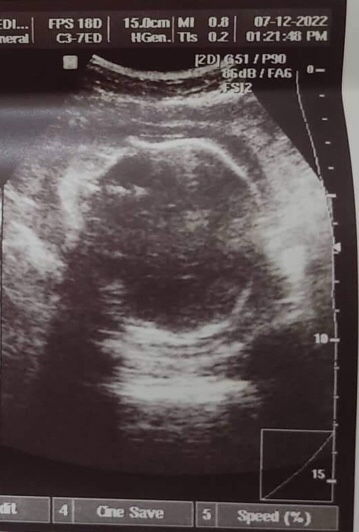

Magbasa pasaakin po irreg ako nag PT ako 5x 2mumurahin 3mamahalin na pt at lahat negative pero di ako nakuntento kaya nag pa transV ako, and dun ko nalaman na buntis ako 3months na ako nun, mas best talaga mag pa transV mare sobrang accurate at makikita mo kung may problema ka ba sa matres o sadyang buntis ka na pala

gaano na po kayo katagal delayed if 2 weeks or more dpt po positive na sa PT. If di kampante sa pt better OB + transv po tlga hindi po kse namen kayo ma didiagnose at di din po kayo ma didiagnose ng OB nyo kung di po nya makikita thru transv and uterus nyo.